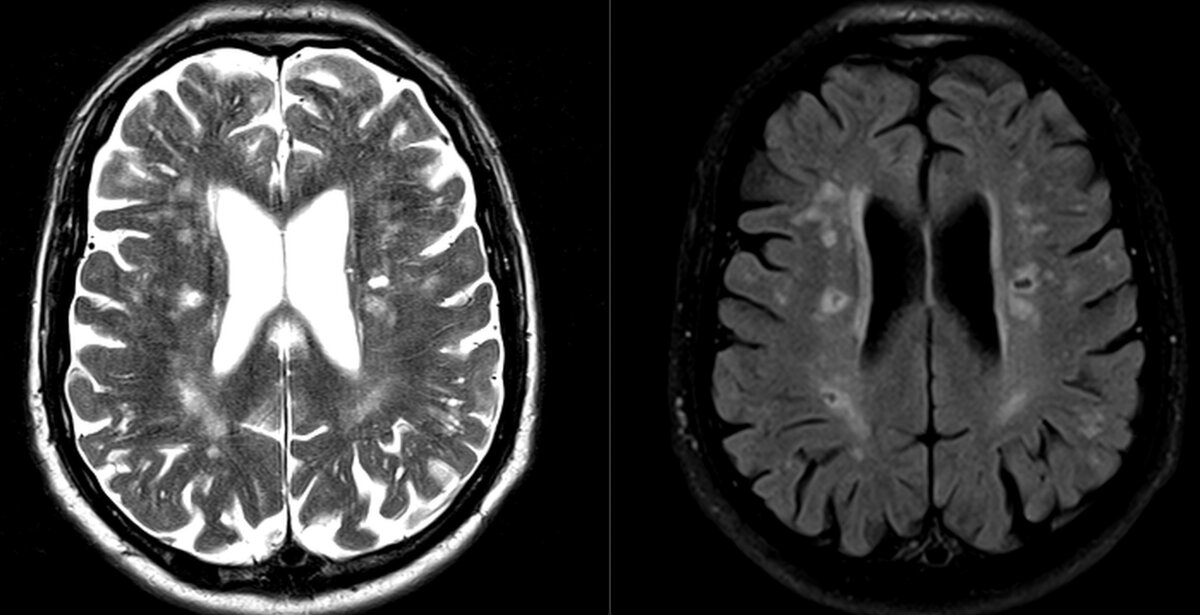

Мужчина 65 лет (только выходит на пенсию), обратился к нам для проведения МРТ. Перед исследованием, как обычно, спрашиваем что беспокоит.

"Было уже несколько инсультов. Сейчас голова совсем не соображает и память плохая" - жалуется пациент.

На МРТ мозга видим печальную картину: уменьшение объёма мозга (атрофия), множественные очаговые изменения, в т.ч. есть много "дырок", как в сыре:

Эти "пробоины" - лакунарные кисты после множественных инсультов (они возникают, когда прекращается кровоток в мелких сосудах из-за бляшек и тромбов).

Как с досадой в таких случаях говорит мой коллега, "очередная трухлявая голова".

С первого взгляда на МРТ нам понятно, что у человека серьёзные проблемы с сосудами. Сам по себе мозг к 60 так сильно "испортиться" не может, ему надо "помочь".